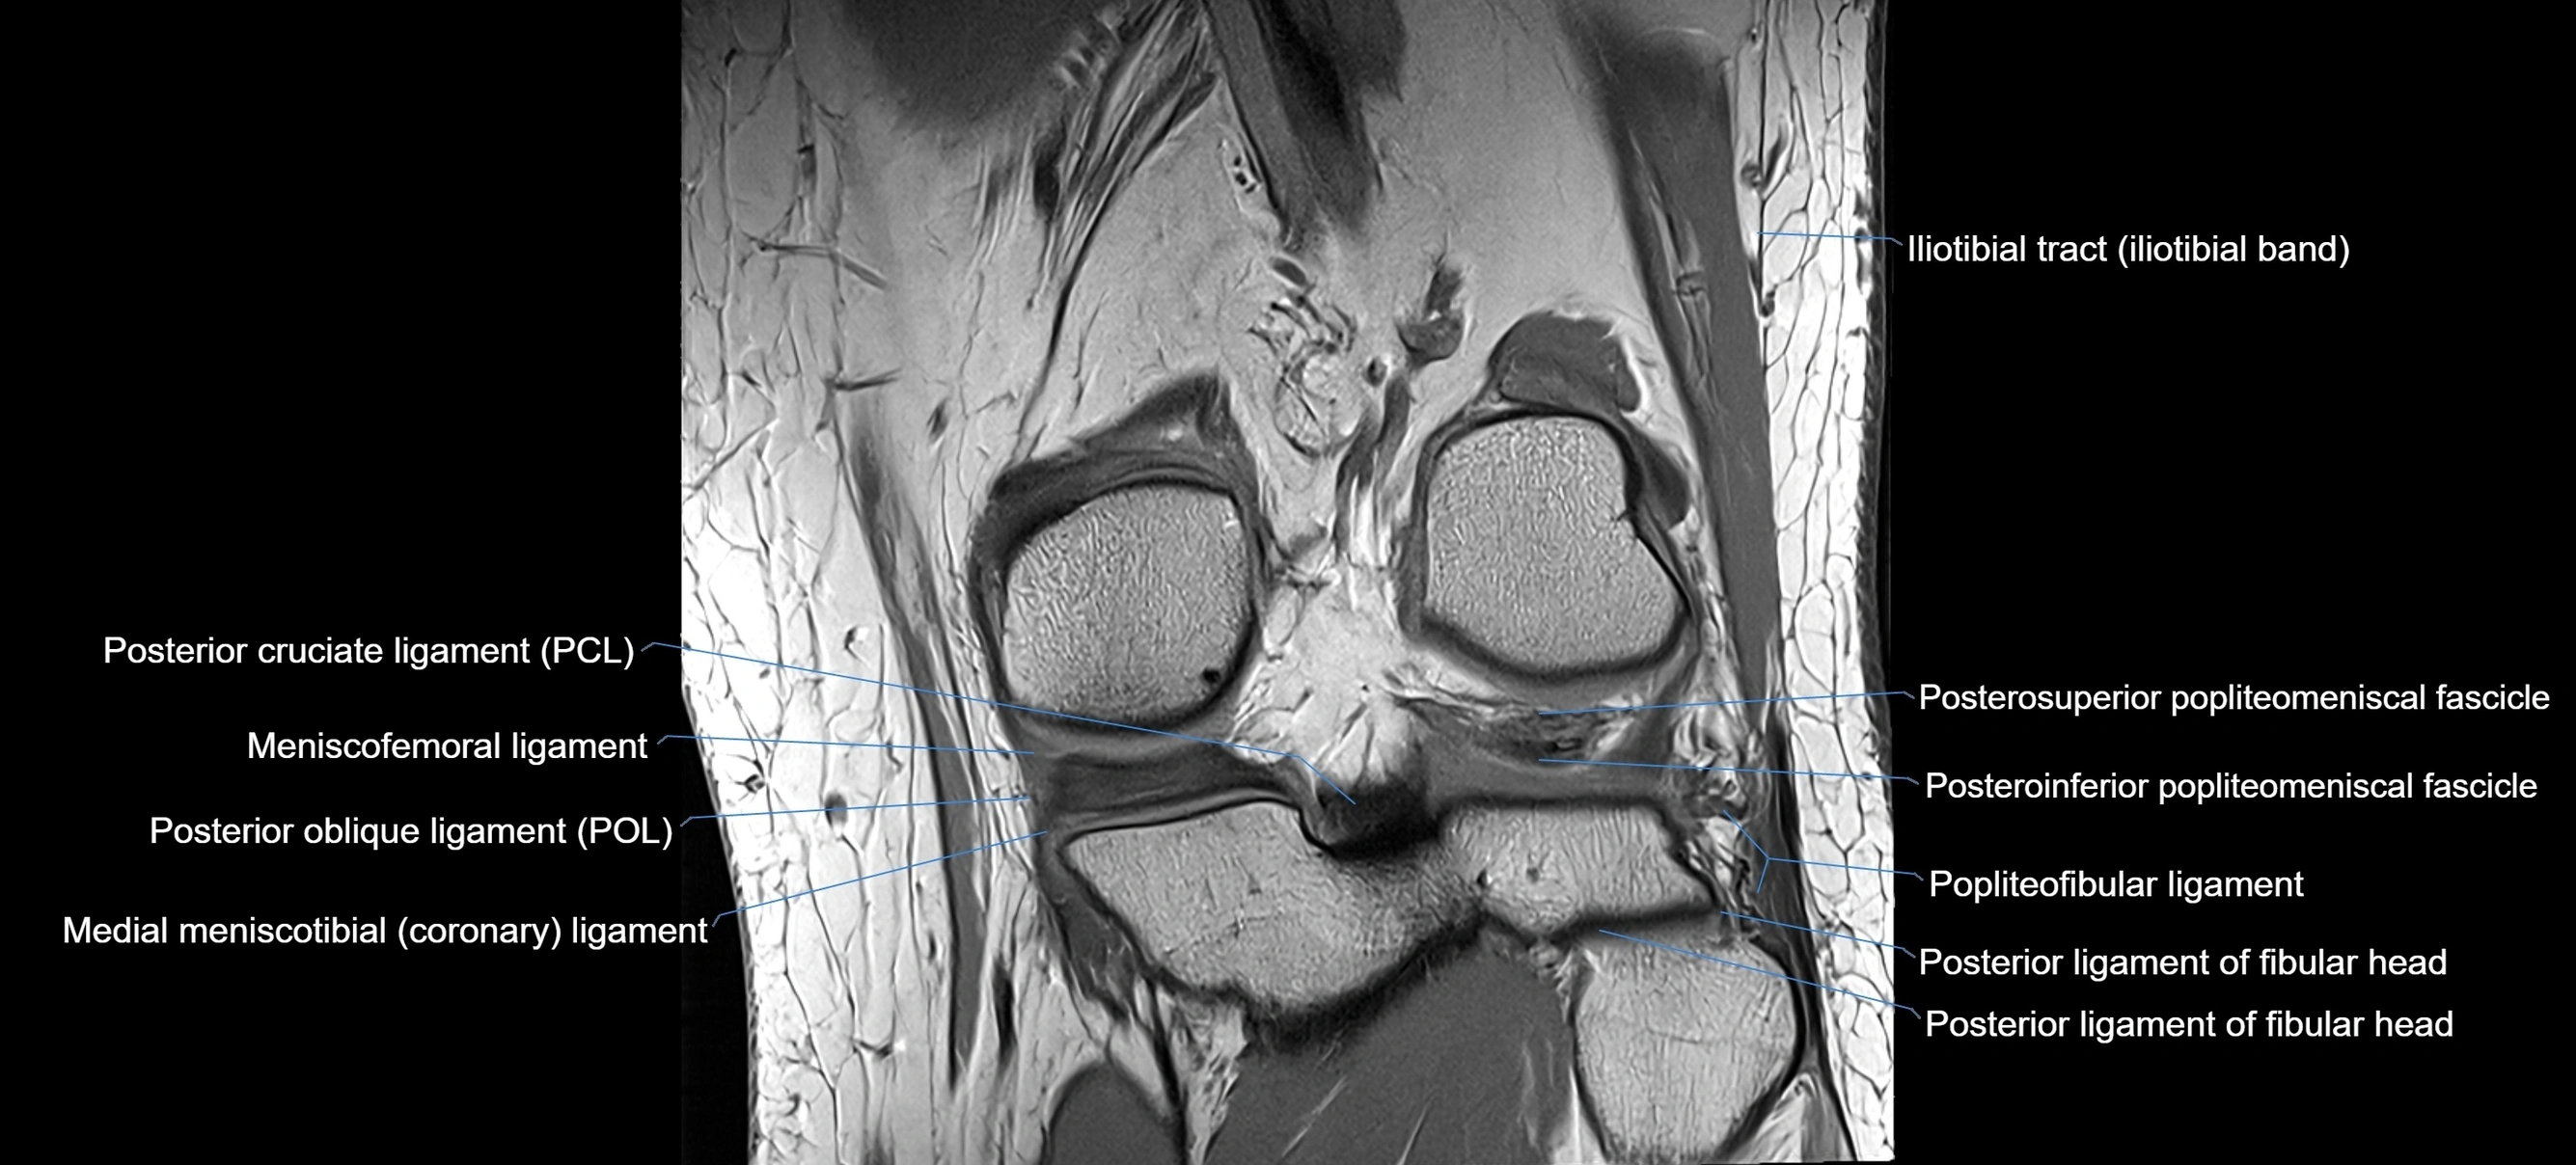

MRI images

image